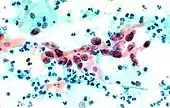

The stain should result in cells that are fairly transparent so even thicker specimens with overlapping cells can be interpreted.[2] Cell nuclei should be crisp, blue to black on color[12][13] and the chromatin patterns of the nucleus should be well defined. Cell cytoplasm stains blue-green and keratin stains orange in color.[13][5]

Eosin Y stains the superficial epithelial squamous cells, nucleoli, cilia, and red blood cells.[2] Light Green SF yellowish confers a blue staining for the cytoplasm of active cells such as columnar cells, parabasal squamous cells, and intermediate squamous cells.[14] Superficial cells are orange to pink, and intermediate and parabasal cells are turquoise green to blue.[12]

Squamous Cell Carcinoma, bronchial washing..jpg.webp)